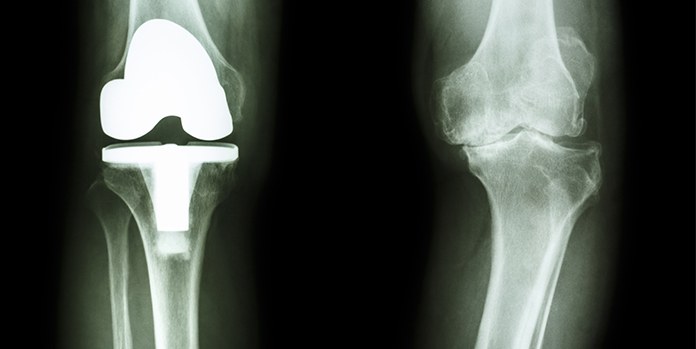

Knee Joint Replacement X-Ray